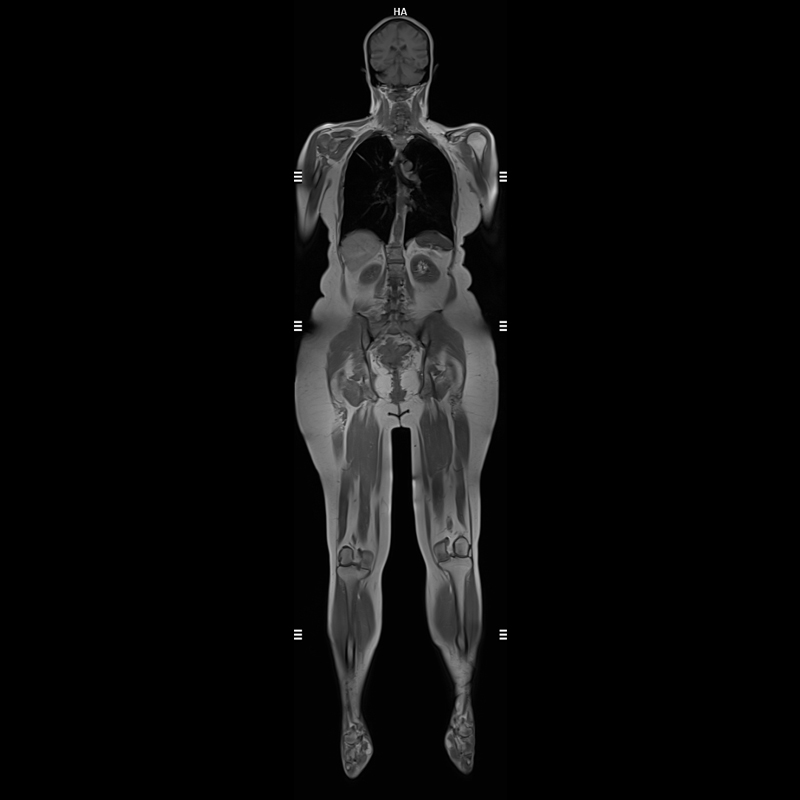

3 Tesla MR Tüm Vücut Görüntülemede Yapay Zeka Destekli Son Teknoloji

Yüksek Görüntü Kalitesi:

Küçük anatomik detayların ve patolojilerin daha iyi tespit edilmesine olanak tanır.

Beyin, omurilik, kas-iskelet sistemi ve yumuşak dokuların değerlendirilmesinde üstündür.

1. Yüksek Görüntü Kalitesi:

o Küçük anatomik detayların ve patolojilerin daha iyi tespit edilmesine olanak tanır.

o Beyin, omurilik, kas-iskelet sistemi ve yumuşak dokuların değerlendirilmesinde üstündür.